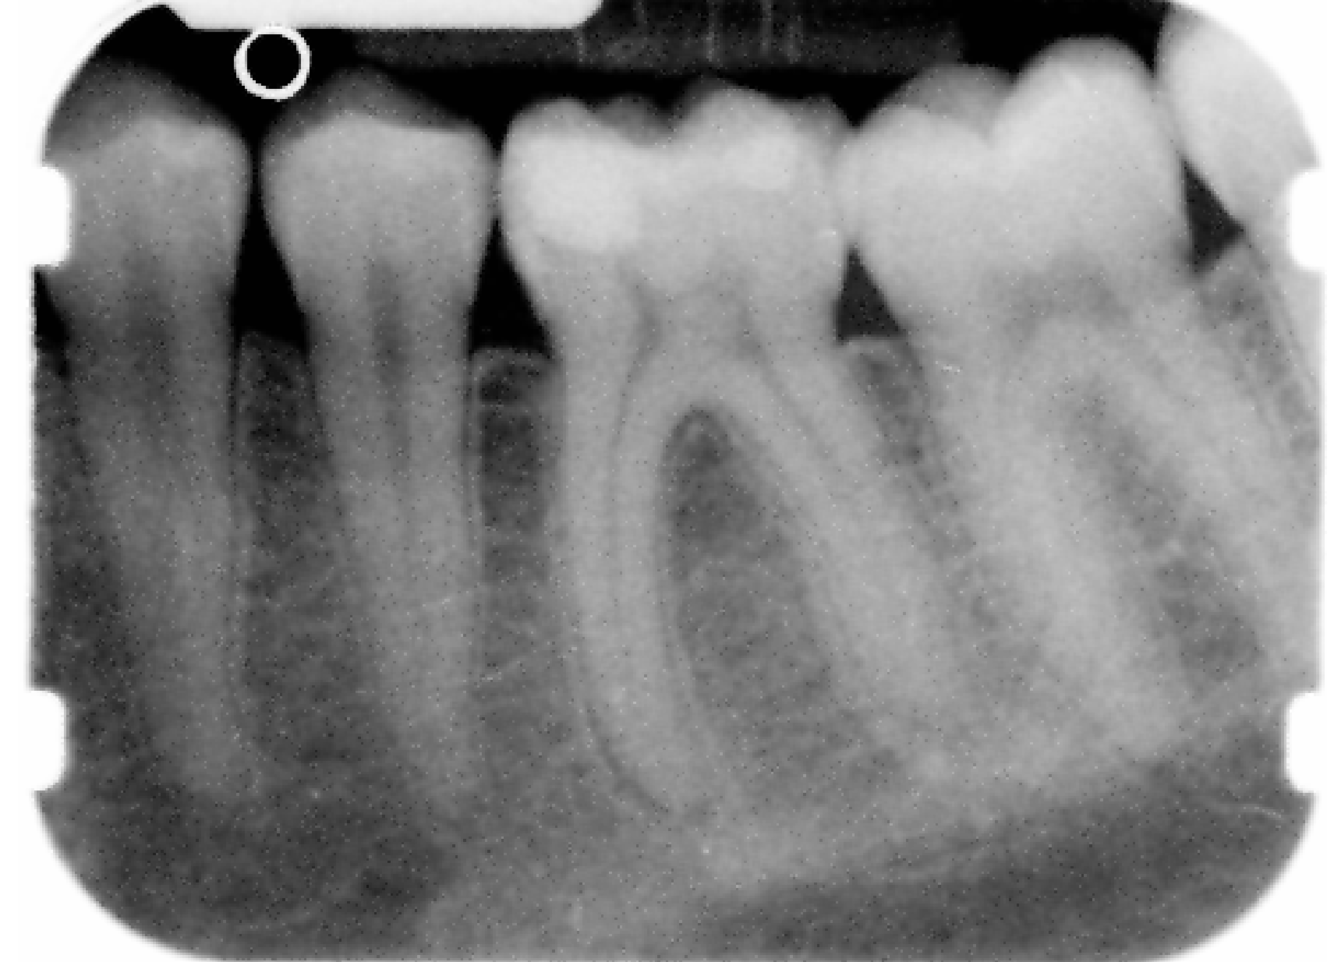

What are the similarities between Bitewings and paralleling periapicals?

When would you use Bitewing Radiograph?

What are the 3 most important features in Radiology & peri-radicular disease?

These 3 are key to interpretation of radiographs BUT can be lost due to personal variation & Limitation due to:

What is Radiographic appearance of periapical pathology such as Initial acute inflammation?

Initial acute inflammation

What can you see at the Initial spread of inflammation?

Loss of lamina dura at apex

What can you see in Further inflammatory spread?

Periapical bone loss